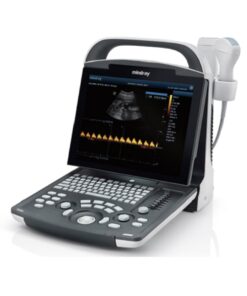

FUJIFILM ARIETTA 750 VE – Ultrasound System

FUJIFILM ARIETTA 750 VE – Diagnostic Ultrasound System

ARIETTA 750 VE ultrasound. What’s your ideal ultrasound experience?

Welcome to the ARIETTA 750. Empower your Ultrasound!

- Great image quality delivered by our latest processing technologies like eFocusing and Carving Imaging.

- Premium, AI-based measurement functions that take patient diagnosis to the next level.

- Excellent probe coverage for a wide range of therapeutic areas.

Choose the ARIETTA 750 and you get high image quality delivered with a choice of different options. But perhaps most importantly, the ARIETTA 750 puts you firmly in charge of your patients’ diagnostic data through advanced measurement technology – including criteria and indices for various organ functions.

The result: diagnose pathologies at the touch of a button, more efficiently than ever before.